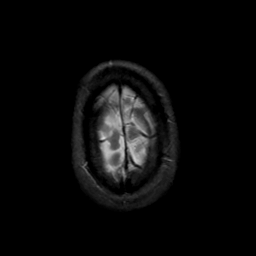

MR Study #17, July 7, 1991 -- Slice #46